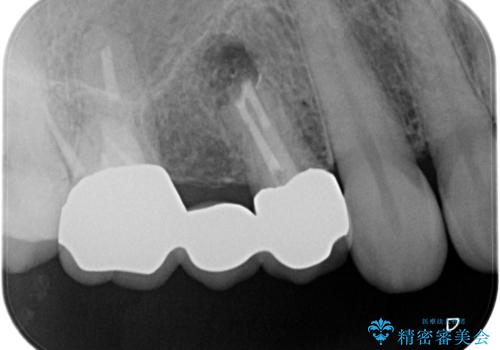

歯肉を押すと痛みがあり、レントゲンの画像でも病変があることがわかります。

前医にてラバーダムを用いた根管治療が完了していたため、歯根の先端を切除する治療を行いました。

6ヶ月経過し、症状もなくなり、病変も縮小していることが確認できます。